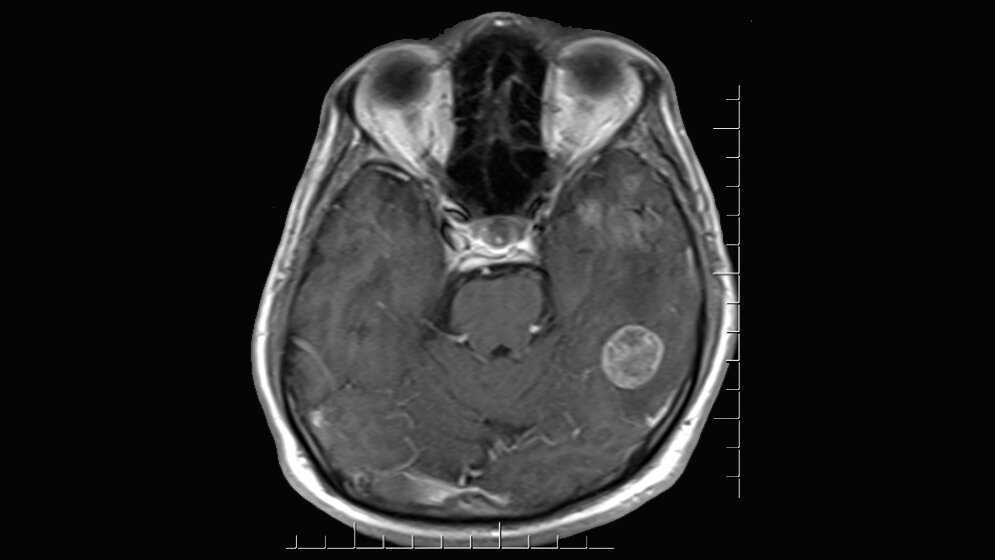

„Viele Patienten schrecken deshalb vor einer Strahlentherapie zurück, obwohl diese den Tumor nachweislich für viele Monate zurückdrängen kann“, erläutert Prof. Combs. Eine schonende Alternative gegenüber der Ganzhirnbestrahlung ist die hochdosierte, lokalisierte Strahlentherapie, wie die stereotaktische Radiotherapie. Bei der Behandlung werden Komplikationen weitestgehend vermieden durch die Behandlung mit einem Spezialgerät, welches eine punktgenaue Bestrahlung ermöglicht. Durch eine präzise, hochauflösende Bildgebung (u.a. Magnetresonanztomographie) wird dieser Punkt vorher bestimmt.

Nach der Entfernung des Tumors kann die Operationshöhle dann bestrahlt werden. „Diese Behandlung ist dann ganz fokussiert auf die ehemalige Metastasenregion. Wir sprechen von einer fokalen Bestrahlung, die in nur wenigen Behandlungstagen durchgeführt wird, in vielen Fällen sogar ohne einen Krankenhausaufenthalt“, erläutert Professor Combs. Diese Art der Bestrahlung sei besonders schonend für die restlichen Regionen des Gehirns, wodurch kognitive Störungen weitestgehend vermieden werden können, so Combs. Dabei bezieht sie sich auf zwei aktuelle Studien.